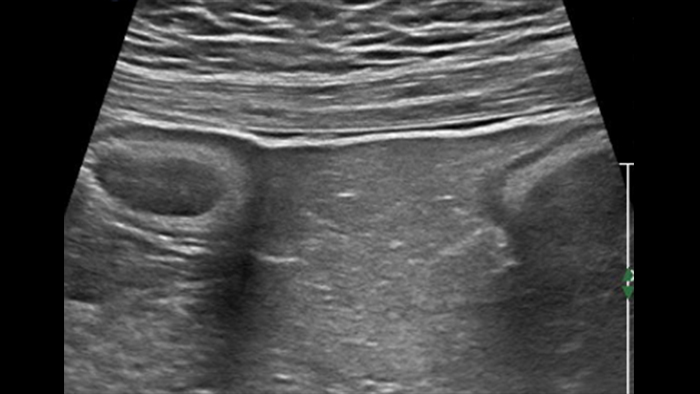

Cet aspect est constant dans tout l’intestin grêle et le côlon. Si l’épaisseur pariétale est variable, elle demeure cependant toujours inférieure à 5 mm. La ligne muqueuse peut être linéaire ou ondulée en présence de villosités ou de plis. Par ailleurs, le péristaltisme peut gêner l’identification des couches. La nouvelle sonde eL18-4 offre de manière complémentaire la haute résolution et la cadence d’acquisition requises pour pouvoir visualiser nettement les couches de la paroi intestinale. A titre d’exemple, voici un comparatif de la maladie de Crohn et de la rectocolite hémorragique (même échelle) :

Dans les formes tardives de la maladie de Crohn, la différenciation des couches a tendance à s’estomper avec le développement d’une fibrose transmurale et devient ensuite invisible. La scléro-lipomatose du tissu adipeux mésentérique adjacent est hypertrophique et a un aspect en verre dépoli. Les fistules actives se présentent sous forme de trajets hypoéchogènes linéaires entre la paroi digestive et la scléro-lipomatose.